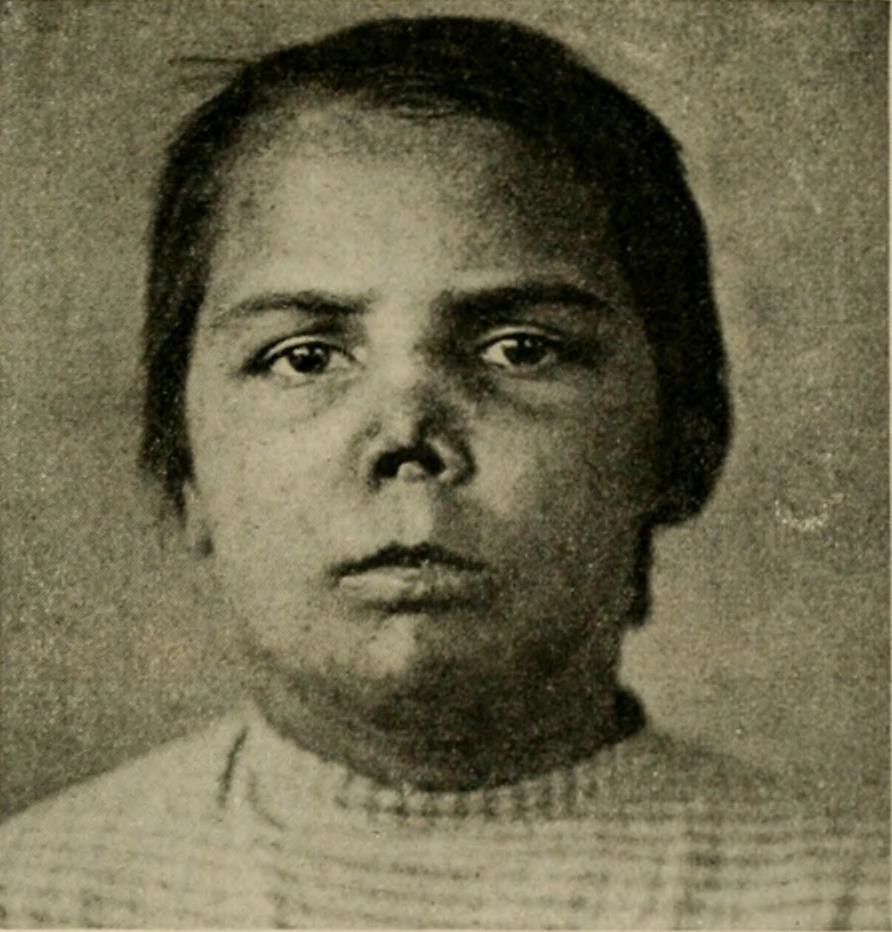

Syphilis Face / Shocking Photos Of Syphilis Victims Before Penicillin …

Photograph from ‘Atlas of Syphilis and the Venereal Diseases’ , 1898 …

This image is taken from Atlas of syphilis and the venerea… | Flickr